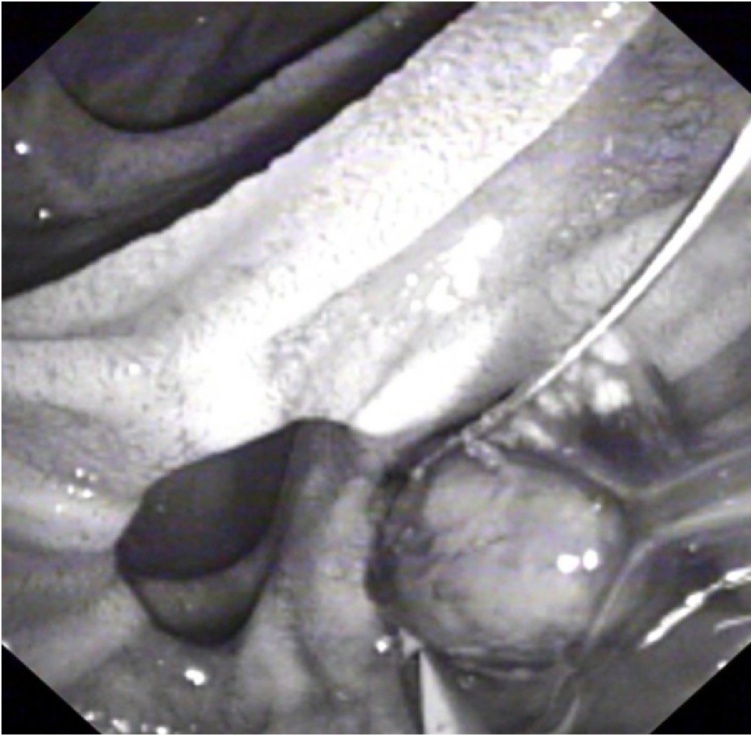

Three days following admission, the patient developed cholestatic jaundice and fever. Liver biochemistry showed the following values: total bilirubin 48 gm/dl (N: <21 gm/dl), gamma-glutamyl transferase 771 U/L (N: 8–61 U/L), alkaline phosphatase 140 IU/L (N: 40–129 IU/L), aspartate aminotransferase 175 IU/L (N: 10–40 IU/L), and ALT 182 U/L (N: 8–41 U/L). The patient was transferred to a specialized endoscopy centre. Urgent ERCP revealed a solitary mid-CBD filling defect encasing a linear metallic radiodensity consistent with a gallstone and embedded endoclip (Fig. 3). Medium-sized sphincterotomy was successfully performed, and the stone and clip were extracted using a retrieval balloon catheter (Extractor™ Pro RX, Boston Scientific, Cork, Ireland) and released into the duodenum (Fig. 4). Gross examination of the stone revealed a closed endoclip.

Diagnosis of ECM requires high index of clinical suspicion and is frequently made at the radiological level. Serial abdominal radiographs and cross-sectional imaging can prove helpful in detecting early displacement of endoclips, and the term “cat’s eye calculus” is often used to denote the endoclip-stone appearance on CT scan [ref. 15]. ERCP remains the gold standard to confirm the diagnosis and along with sphincterotomy offers the best treatment modality with success rate of 85% [ref. 2]. Both balloon catheter or wire basket can be safely used for endoclip-stone retrieval. Surgical exploration and percutaneous transhepatic cholangiography should be reserved as rescue procedures for cases in which endoscopic therapy is either not feasible or fails [ref. 16]. The latter could be due to the unfavourable endoclip-stone orientation within the CBD or the presence of biliary strictures, fistulas, or large stones [ref. 2,ref. 17].